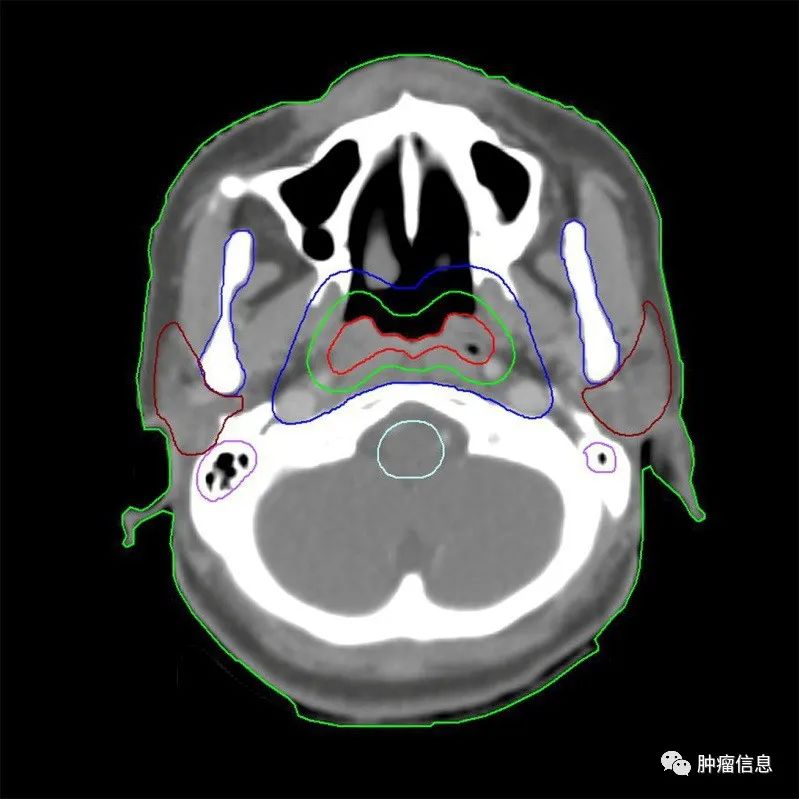

2.靶区勾画示意图

为方便和国际指南对照,靶区采用与国际指南相同的颜色:国际指南的GTVp =本示意图GTVnx;国际指南的GTVn =本示意图GTVnd;国际指南的CTV1 =本示意图CTV1;国际指南的CTV2 =本示意图CTV2。

图1 T1N0M0

(注:靶区勾画颜色, GTVnx为红色,CTV1为绿色,CTV2为蓝色。)